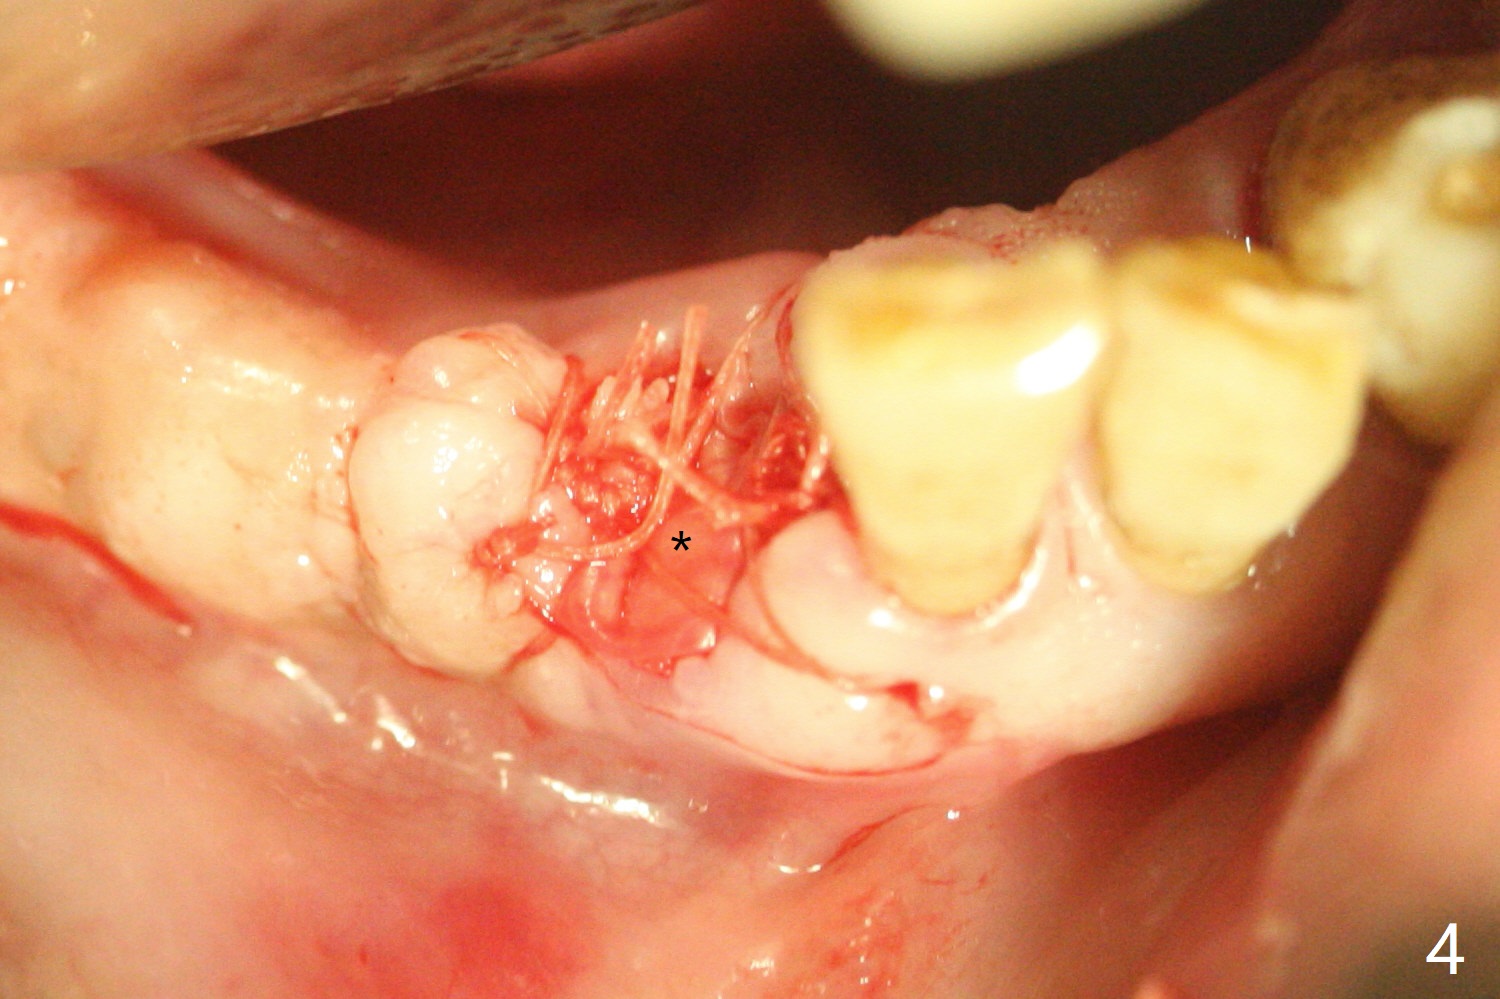

The 58-year-old man returns for #25 extraction while the redo implant at #12 is osteointegrating (Fig.1-3). After discussion, he agrees with socket preservation with 8x8 mm BioXclude (Fig.4 * (4-0 PGA)) and Vanilla graft (Fig.5 *). The socket is healing 6 days postop (Fig.6).